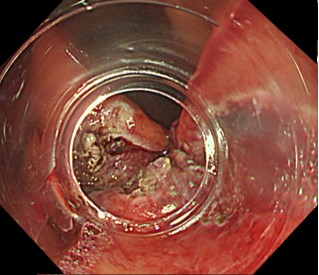

内視鏡で胃と食道のつなぎ目の粘膜を切除して、修復過程で狭くなることを利用して、逆流を防止します。